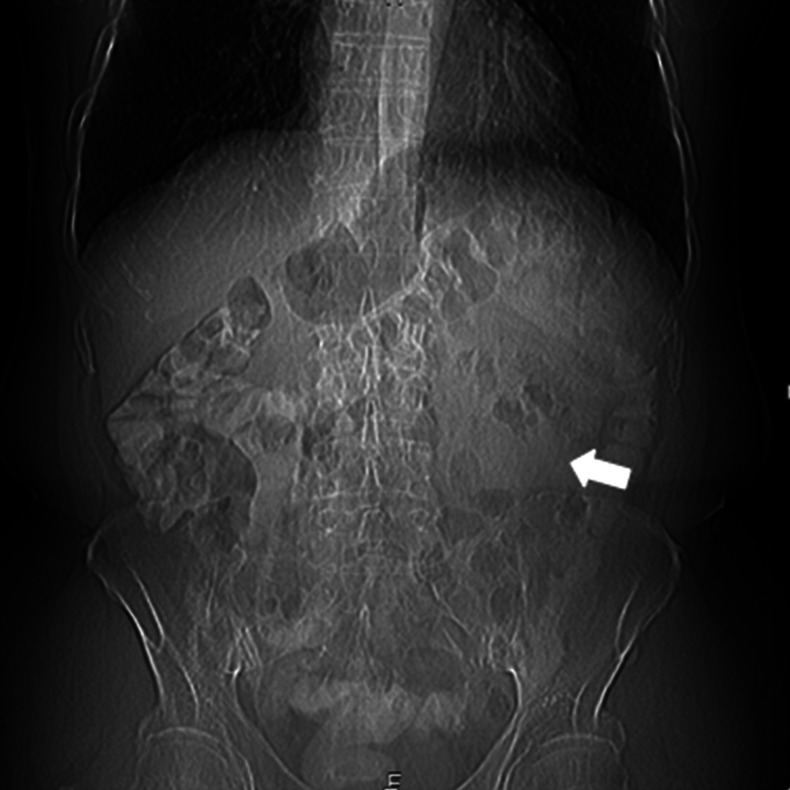

Figure 1.

CT scanogram showing displaced bowel loops (arrow) in the left upper abdominal quadrant.